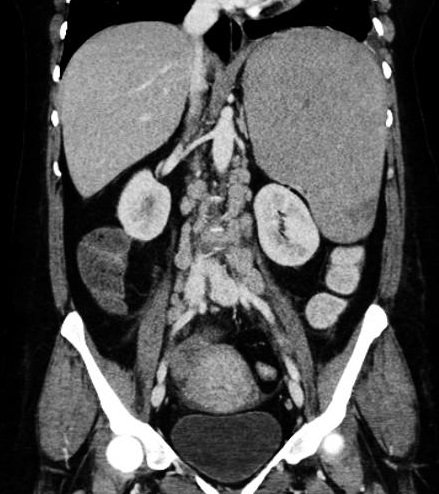

Aspect

radiologique une rate sur numeraire a inferieure de

la la rate principale ( fleche rouge ) .Ce coupe

frontale ( coronal) se prise au temps de precoce

apres injection de contrast intra veineuse . Sa

parenchyme est rehaussement hyperdensité heterogène

au temps de precoce . Image radiologique TDM plus C+

coupe coronal . |